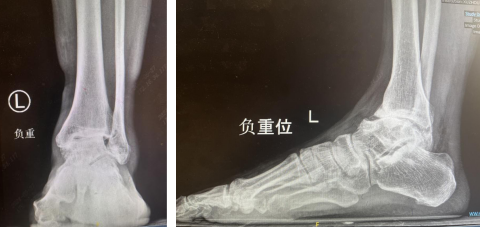

术前X光 可见踝关节终末期踝关节炎改变——“报废”关节

通过检查,患者左踝关节骨性关节炎、并且X光显示踝关节退变非常严重,软骨大部分出现了磨损,保守治疗难以达到理想效果,手术指征明确。